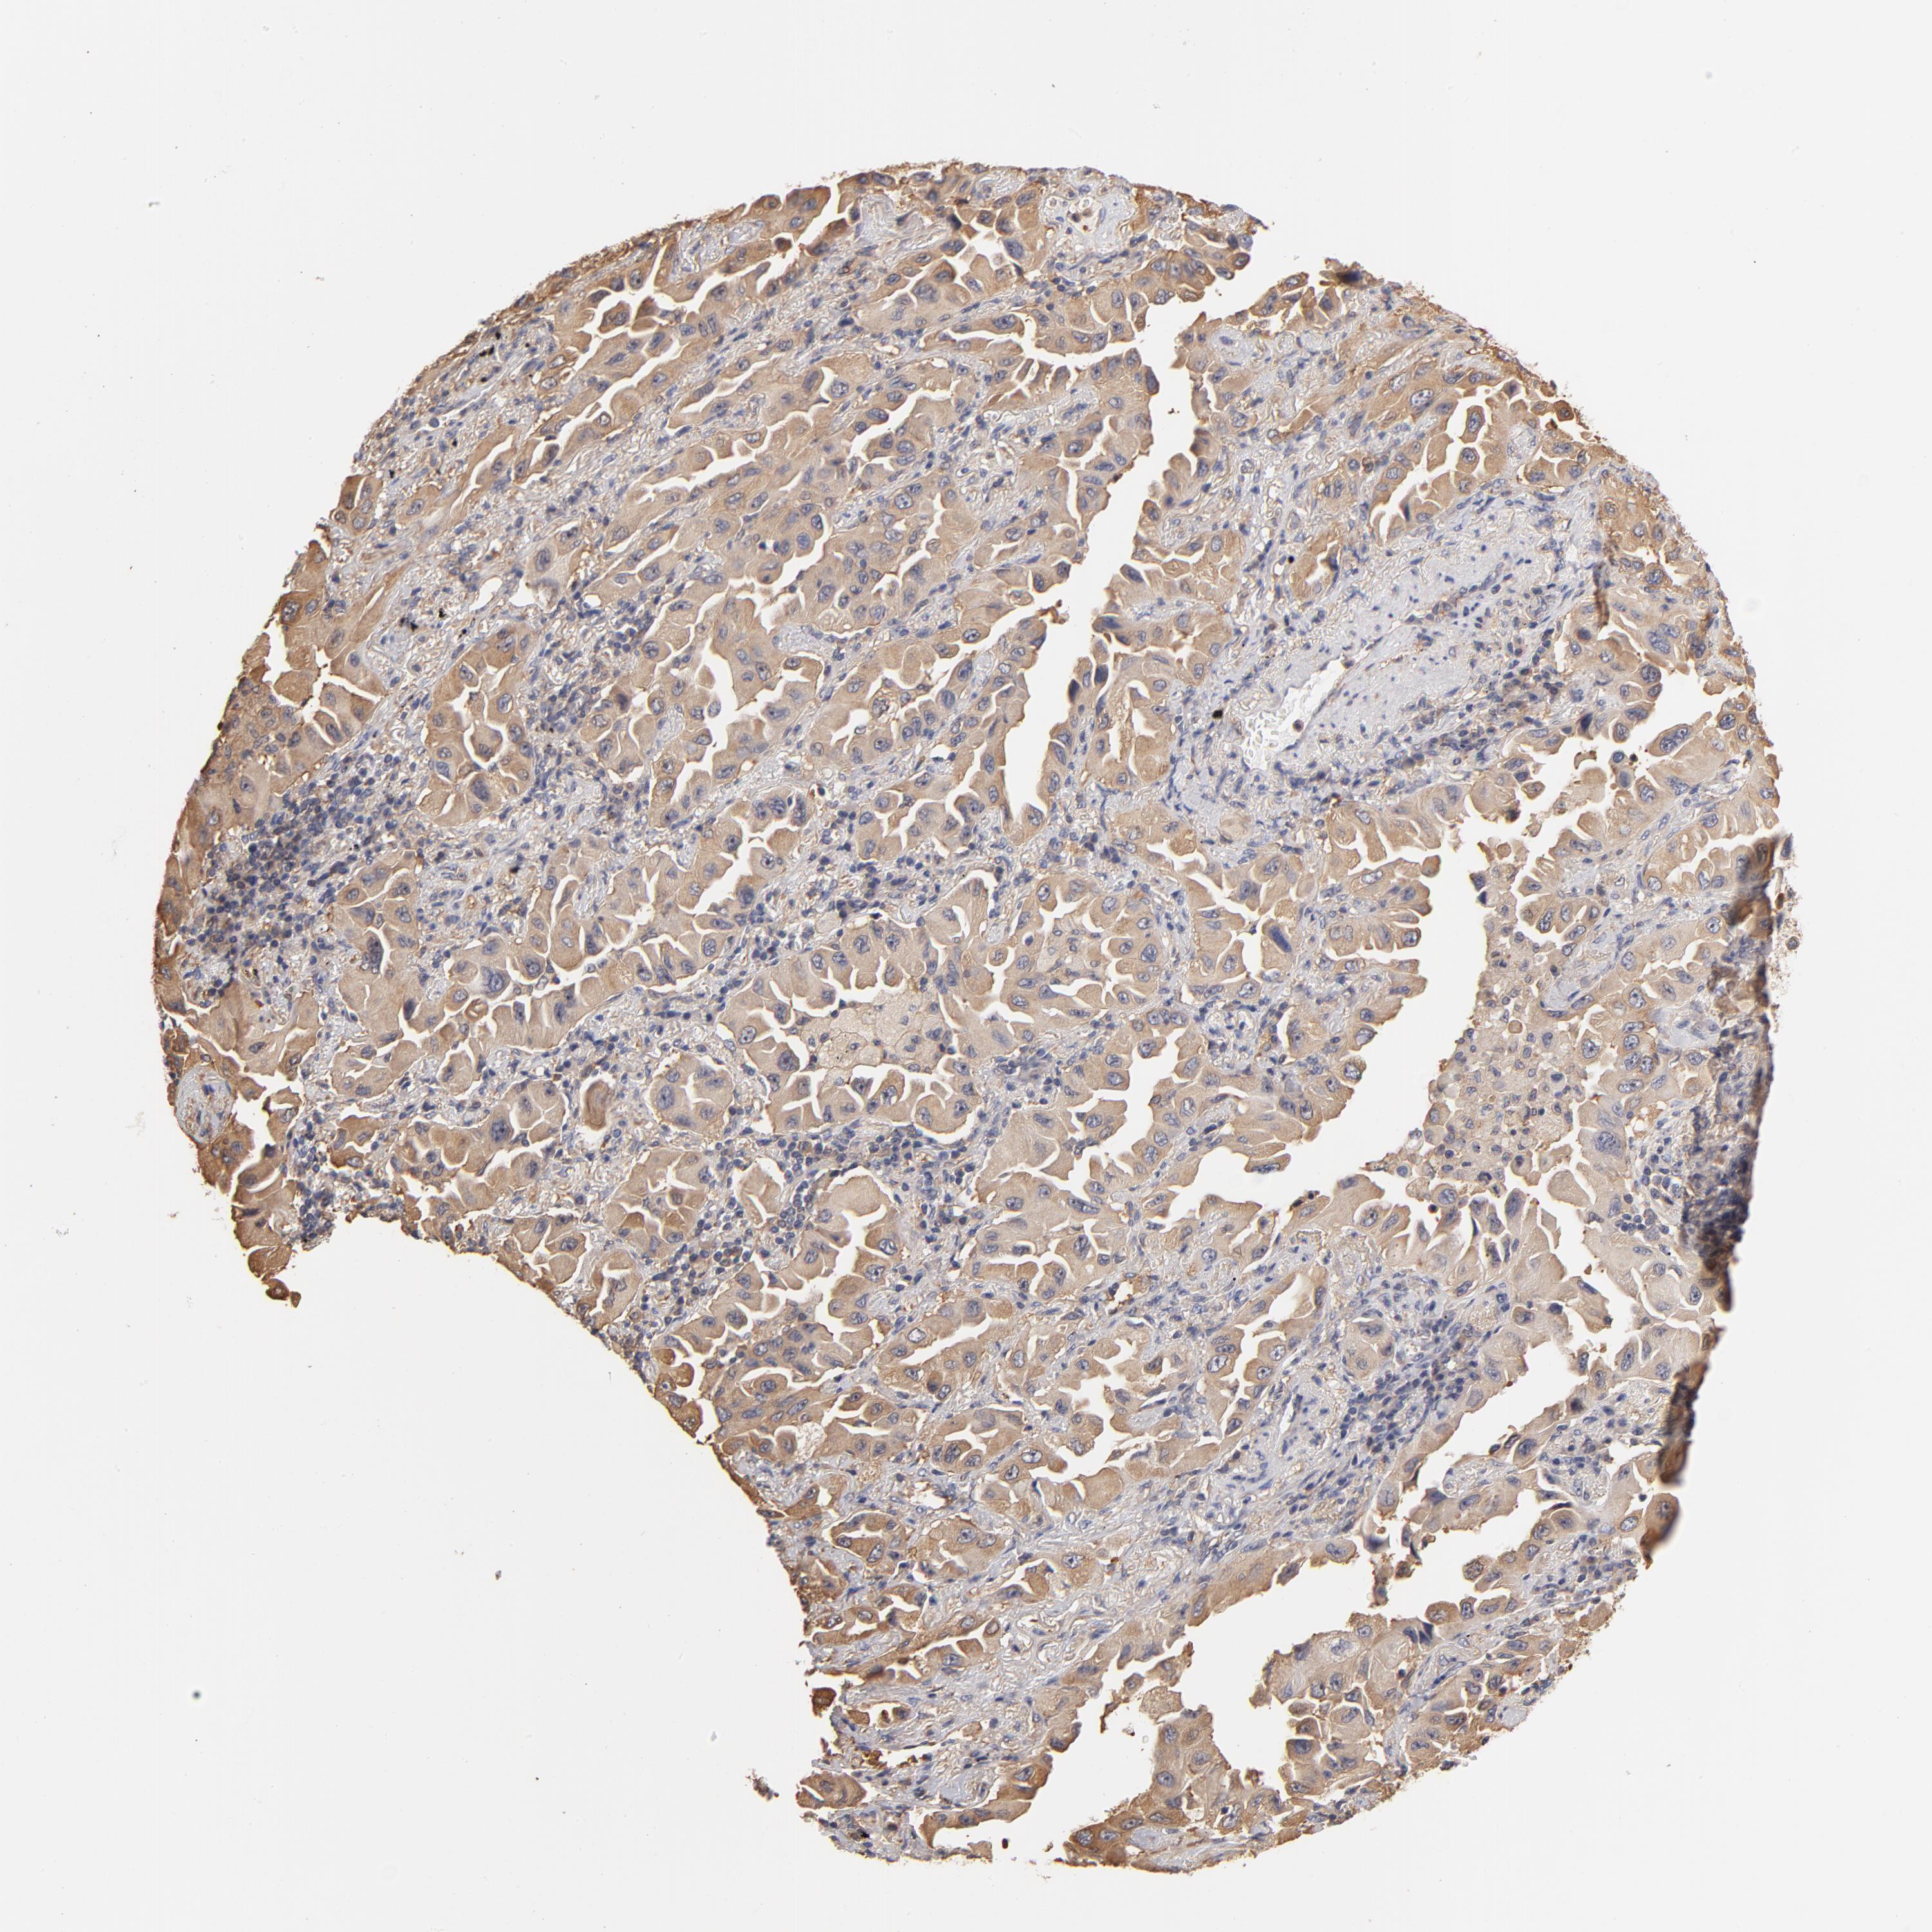

CANCER LUNG CANCER Show tissue menu

LUAD TCGA LUAD VALIDATION LUSC TCGA LUSC VALIDATION PROTEIN LUAD CPTAC PROTEIN LUSC CPTAC PROTEIN EXPRESSION